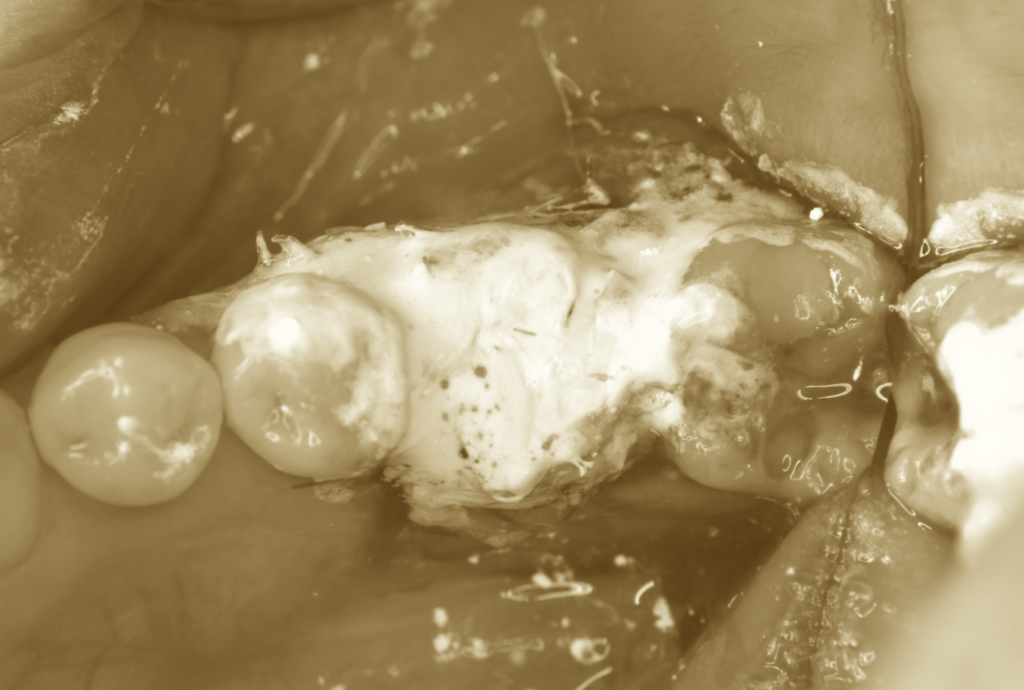

続いて、移植する歯の準備です。

歯根表面に再生療法製剤であるエムドゲインを塗布し、

速やかに移植床へと植立します。

適切な位置に収まっていることを確認したうえで、

縫合により固定を行います。